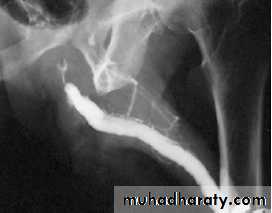

4.Urethrogram or cystourethrogram to assess the site,no. & extent of the stricture + to show some complications as bladder trabeculation,vesical stones & urethral fistula.